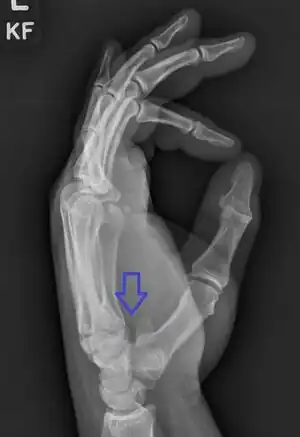

Hamate fracture

Hamate fracture is a break of the hamate bone in the wrist. Symptoms include pain in the front of the wrist in line with the little finger.[1] It is made worse by gripping an object.[1] Complications may include injury to the ulnar nerve and clotting of the ulnar artery.[1]

The cause is typically injury during racket sports, baseball, or golf or a fall onto the hand.[1][2] Types include hook (most common) and body (proximal pole, medial tuberosity, sagittal oblique, and dorsal coronal).[1] Diagnosis is typically by X-rays, but may require special views such as a carpal tunnel or supinated oblique view; or a CT scan.[1]

Treatment when the bones of well aligned is generally orthopedic casting for 4 to 6 weeks; though there is a high risk of it not healing.[1] Otherwise surgery is indicated.[1] For hook fractures surgery generally involves removal of the hook.[1] Hamate fractures represent about 2% to 5% of breaks of bones within the wrist.[1][2]